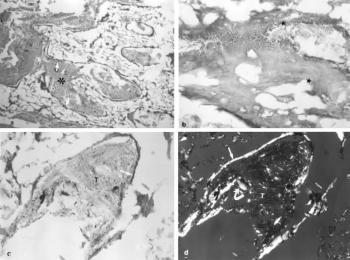

67. ábra. a) A nem calcificált tumoros részeket (csillag) vékony cspontlemez veszi körül. Pikrosziriusz festés 100× nagyítás b) Osteolyticus kirágottság (csillag) a csontgerenda maradványon. HE festés, 200× nagyítás c)–d) A tumoros spiculum centrumában kevés kollagénrostot tartalmazó alapállomány (T), körülötte vékony, daganatos csontlemez figyelhető meg. Pikrosziriusz festés, 240× nagyítás. c) kép fény, d) kép ugyanezen terület polármikroszkópos felvétele